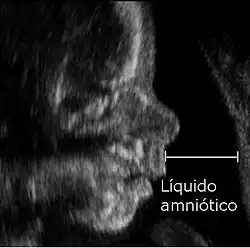

El índice de líquido amniótico (ILA) es una evaluación de la cantidad de líquido amniótico en una mujer embarazada, y es un indicador de bienestar fetal. Es la parte más utilizada del perfil biofísico. Se obtiene con un ultrasonido, mediante la medición en centímetros del diámetro vertical mayor de cada uno de los cuatro cuadrantes uterinos y luego la adición de estas cuatro medidas.[1] También se puede hacer la exploración única, siempre mediante ecografía, realizando una medición única del diámetro vertical o transversal del mayor cuadrante de líquido amniótico que esté libre de partes fetales y cordón umbilical.[2] El ILA es útil porque se correlaciona de una manera muy aproximada al volumen real de líquido amniótico, y es útil en el diagnóstico de las alteraciones en su cantidad y pensamiento.[3]